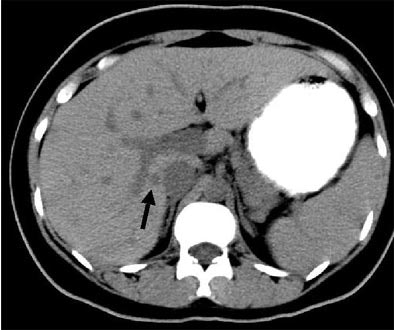

| Another patient with fever after prolonged neutropenia. Above, arterial-phase CT shows a type 2b lesion (arrow). Below, portal-venous phase fails to show a lesion. |

![]() |